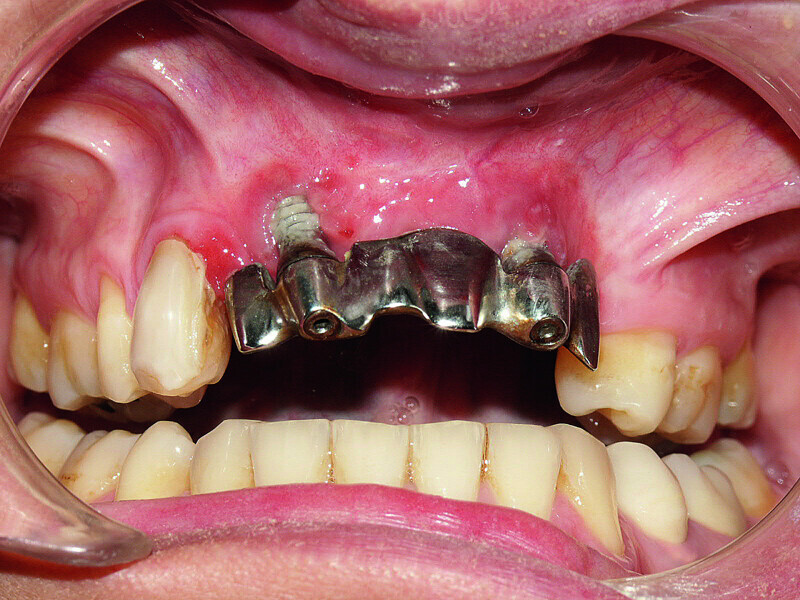

Fig. 1 : Initial prostheses: Lip support was ensured by a large false gingiva, and fractured cosmetic material at the right maxillary canine was evident. The patient’s smile showed the prosthetic teeth placed off-centre and an infiltration at the right lateral incisal level.

Fig. 2 : Initial prostheses: Lip support was ensured by a large false gingiva, and fractured cosmetic material at the right maxillary canine was evident. The patient’s smile showed the prosthetic teeth placed off-centre and an infiltration at the right lateral incisal level.